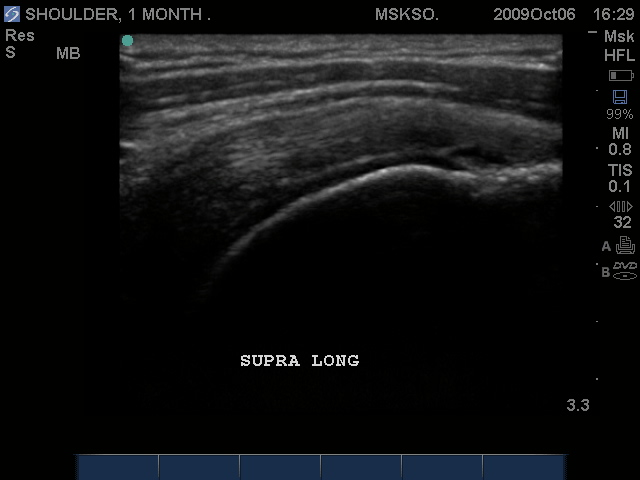

Long axis Supraspinatus tendon over lateral Greater Tuberosity. (lateral greater tuberosity is flat relative to the anterior) Tendon retraction is seen over cartilage interface sign of the humeral head.